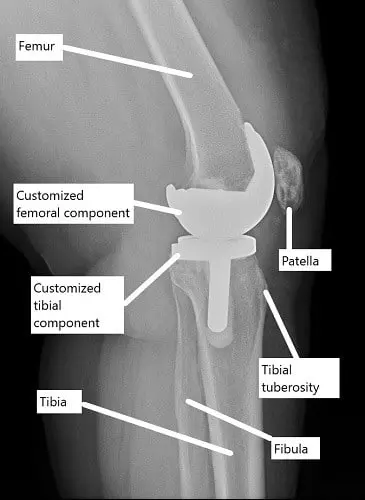

X-ray showing a custom knee replacement.

Customized implants are 3D printed along with customized cutting blocks. The customized implants are made specific to the patient’s natural anatomy of the knee. Unlike generic off-the-shelf implants, these are tailored according to the patient’s biomechanics.

A preoperative CT scan of the patient’s knee and both lower extremities is obtained. A 3D model of the knee anatomy is created with the help of computer software. An assessment of the biomechanical axis of the lower limbs is also made.

The data is then used to create patient-specific cutting blocks to minimize bone loss and ensure accurate placement of the customized implants. The result is a more kinematic knee and patients may experience a more natural-feeling knee joint.